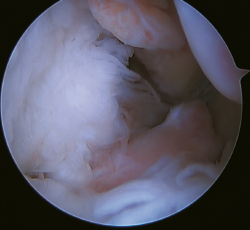

Figure 5. Tearing of the anterior talofibular ligament and calcaneofibular ligament with poor tissue quality of the ligament remnant.